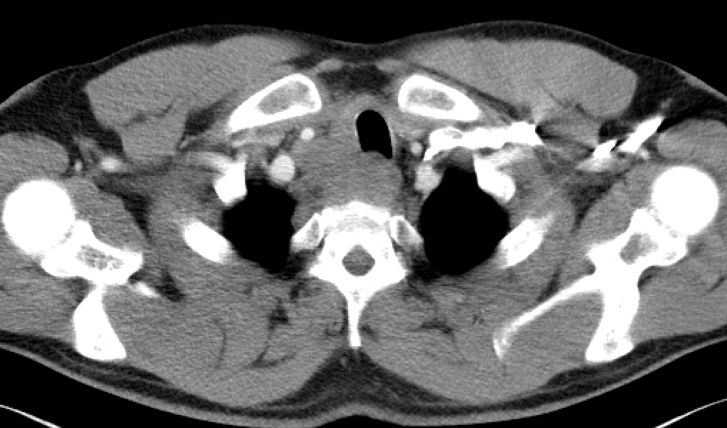

Rezidiv nach Radiochemotherapie eines kleinzelligen Tracheakarzinoms mit großer supraclavikulärer Metastase | |||